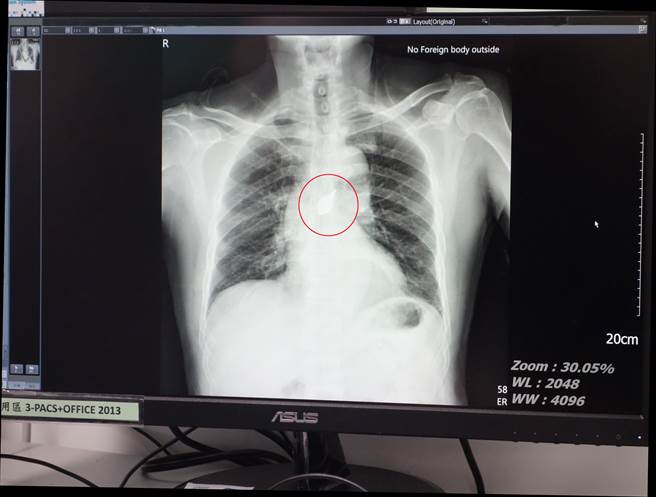

大林慈济胸腔外科医师陈奕中说,病人在急诊检查,发现前胸有2公分穿刺伤,当下还有出血情况,但患者呼吸、心跳及意识都正常,从他自带的院外胸腔X光与电脑断层等检查影像中,发现纵膈腔里有异物,位置刚好卡在心臟与大血管的前面,即前纵膈腔,清楚可见6公分长的刀片。